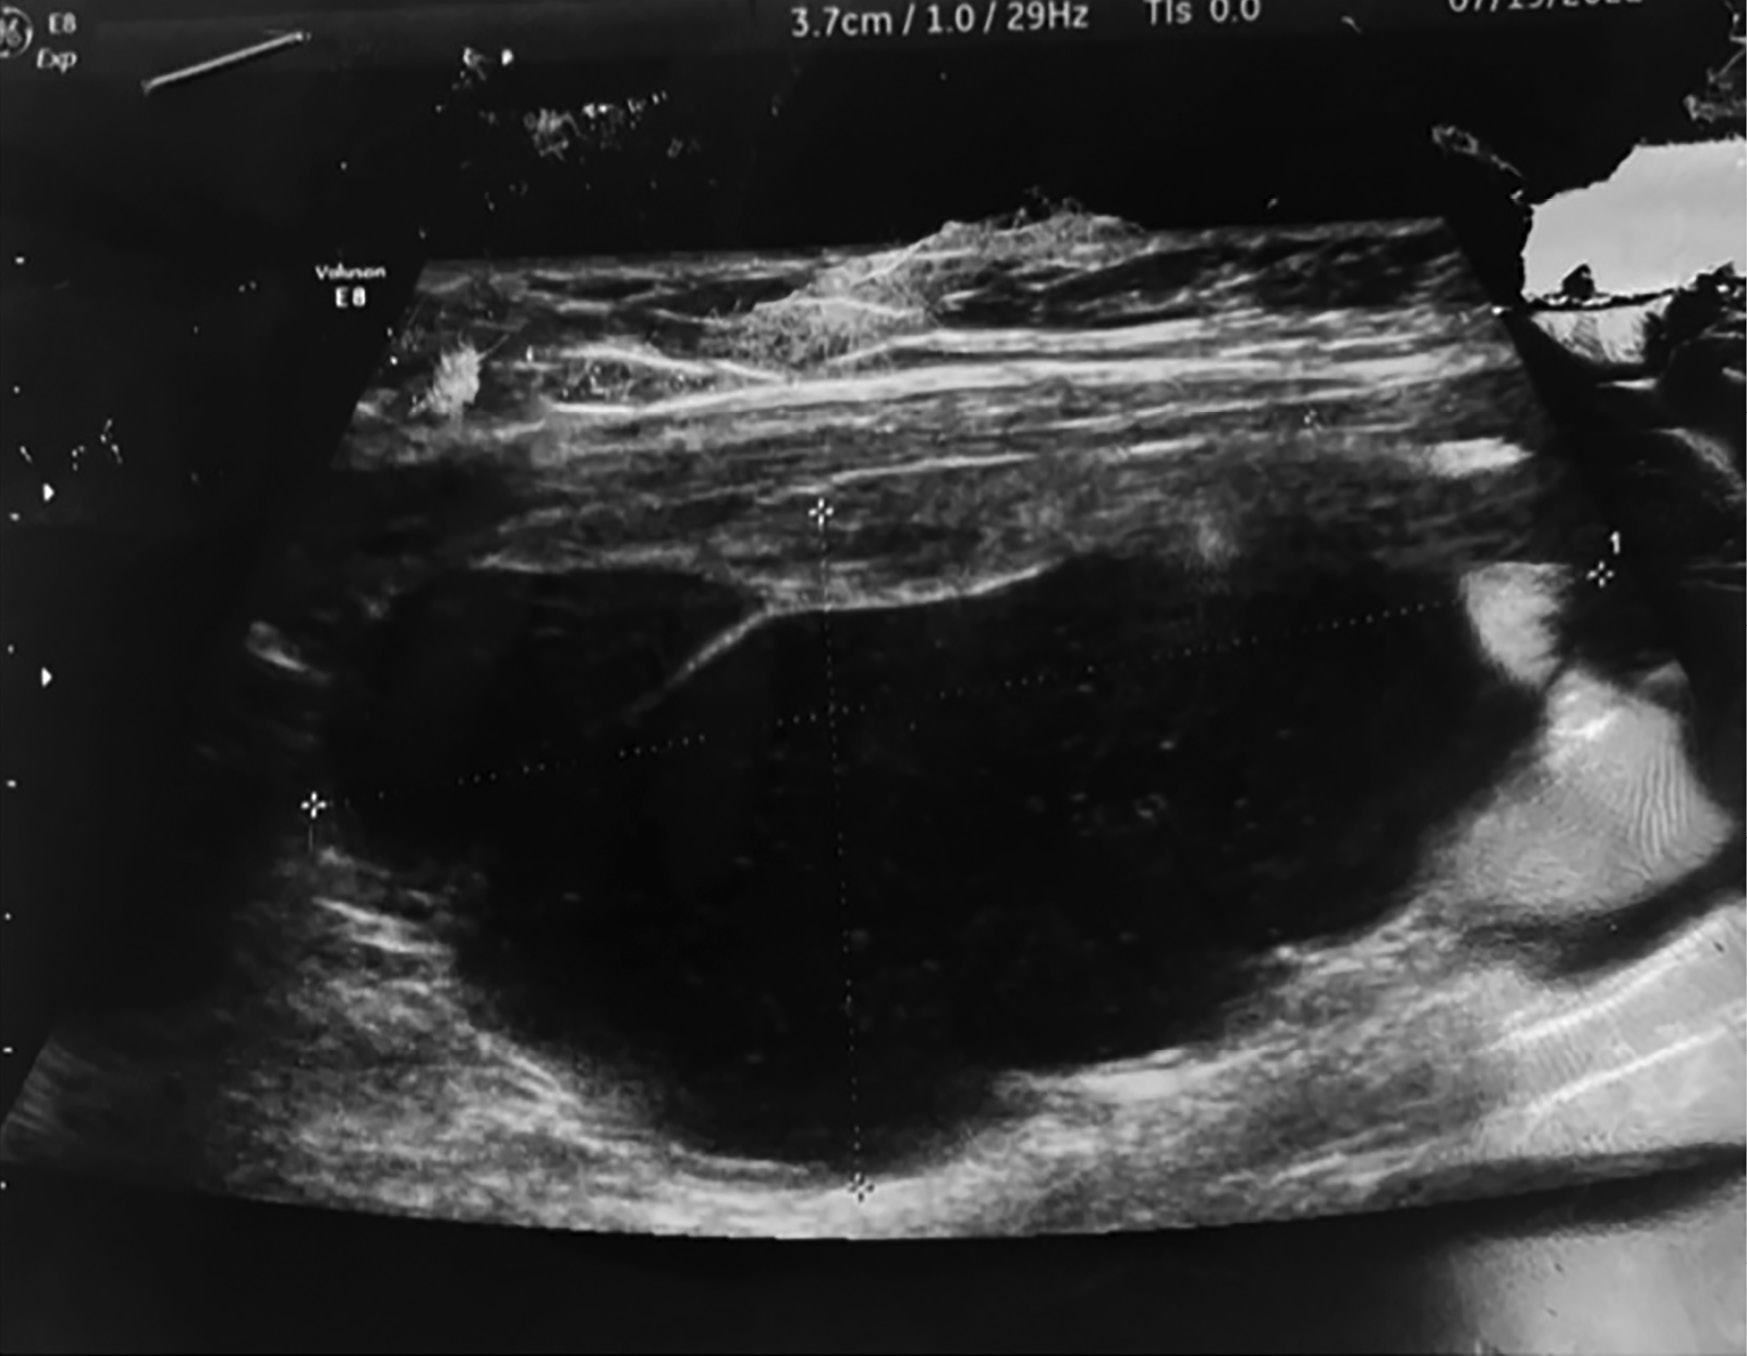

3. Рисунок 3. Ультрасонограмма ЩЖ. В левой доле ЩЖ визуализировано жидкостное новообразование с перегородками, густым содержимым, четкими ровными контурами. | |